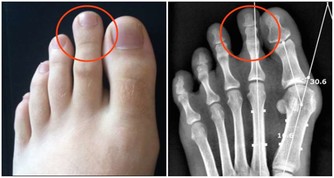

冬季防止寒邪和風邪入侵身體,尤其是做好頭部腳部以及胸腹部的保暖。當寒氣入侵胸腹部時會損傷到陽氣,從而誘發心髒病及胃腸道疾病。天氣寒冷時會讓頭部血管突然收縮,引起頭痛頭暈,增加了患上腦血管疾病的機率,甚至會誘發意外。腳離心臟最遠而且血液供應慢,再加上皮下脂肪層薄,保暖性比較差,當受寒時會引起呼吸道黏膜毛細血管突然的收縮,下降了抵抗力,增加了患上上呼吸道感染的風險。